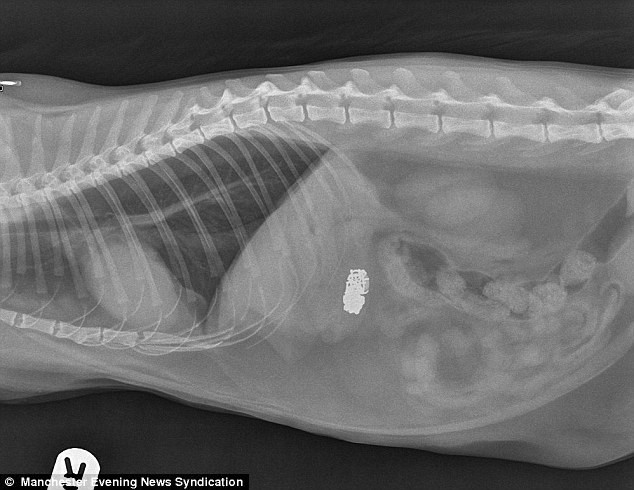

Kết quả chụp X quang thấy rõ viên kim cương trong bụng chú mèo Oliver

Kết quả chụp X quang thấy rõ viên kim cương trong bụng chú mèo Oliver.

Kết quả không ngoài mong đợi. Hình chụp X quang cho thấy, bên trong bụng chú mèo Oliver hiện rõ chiếc vòng tay và viên kim cương. Một cuộc phẫu thuật cho chú mèo Oliver đã lập tức được tiến hành.